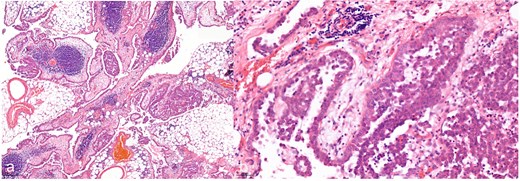

Hematoxylin and eosin staining with a 7.2-fold (a, overview image) and 40-fold (b, detail image) magnification. The histological images show a malignant epithelioid mesothelioma of the peritoneum; atypical tumor cell clusters located in papillary and exophytic formations can be seen.